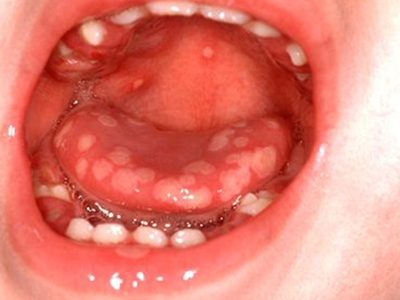

舌头

溃疡

单纯疱疹舌头上有多个散在的溃疡图

单纯疱疹累及舌头,表现为局部有多个散在的白色溃疡面,大小不一,形状不规则,边缘呈锯齿状,但界限清楚,微微内陷。周围有红晕,并微微隆起。

单纯疱疹舌头上有大量白色的溃疡图

单纯疱疹常见于舌头,皮损为密密麻麻的白色溃疡,呈圆形、椭圆形、不规则形等,可由舌头侧缘向舌根部扩展,部分相互融合成片,伴疼痛感。

单纯疱疹舌头上有多个水疱伴红晕图

单纯疱疹特点为患者舌头上有多个水疱,大小不一,呈脐状凹陷或半球形隆起,并在周围有明显的红晕,与周围黏膜界限清楚,自觉疼痛明显。